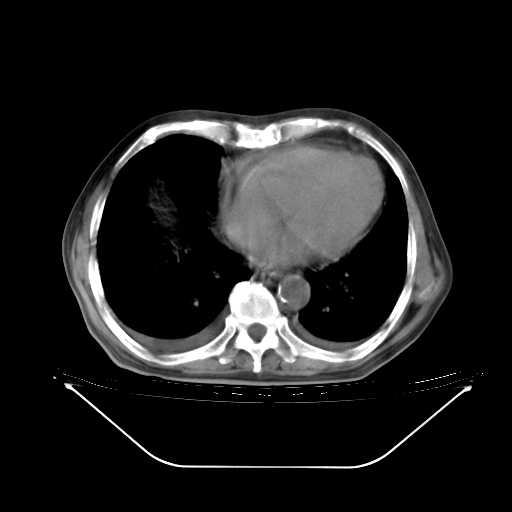

今天复查肺部CT,发现双肺广泛磨玻璃样改变。所以我把3月19日和5月9日相隔50天的肺部CT上传。请大家会诊。

2009年3月19日肺部CT片。

5月9日肺部CT(在4月27日齐鲁医院肺部CT描述部分肺组织磨玻璃样改变,12天后肺组织广泛磨玻璃样改变)